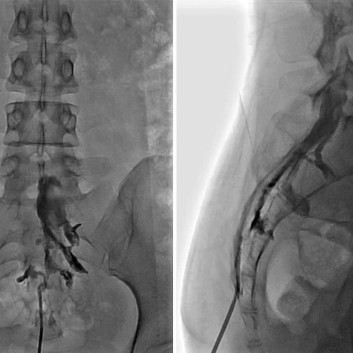

척추 통증의 원인이 되는 돌출 된 디스크나 좁아진 협착이 있는 경우 통증의 원인은 신경 주위의 유착과 부종 및 염증입니다. 경막외 신경성형술은 꼬리뼈에 있는 척추관으로 통하는 구멍으로 직경 1mm 미만의 카테터를 삽입하여 디스크와 협착증이 있는 부위까지 접근시켜 물리적으로 유착을 박리하고 화학적으로 염증과 부종을 줄여줍니다.